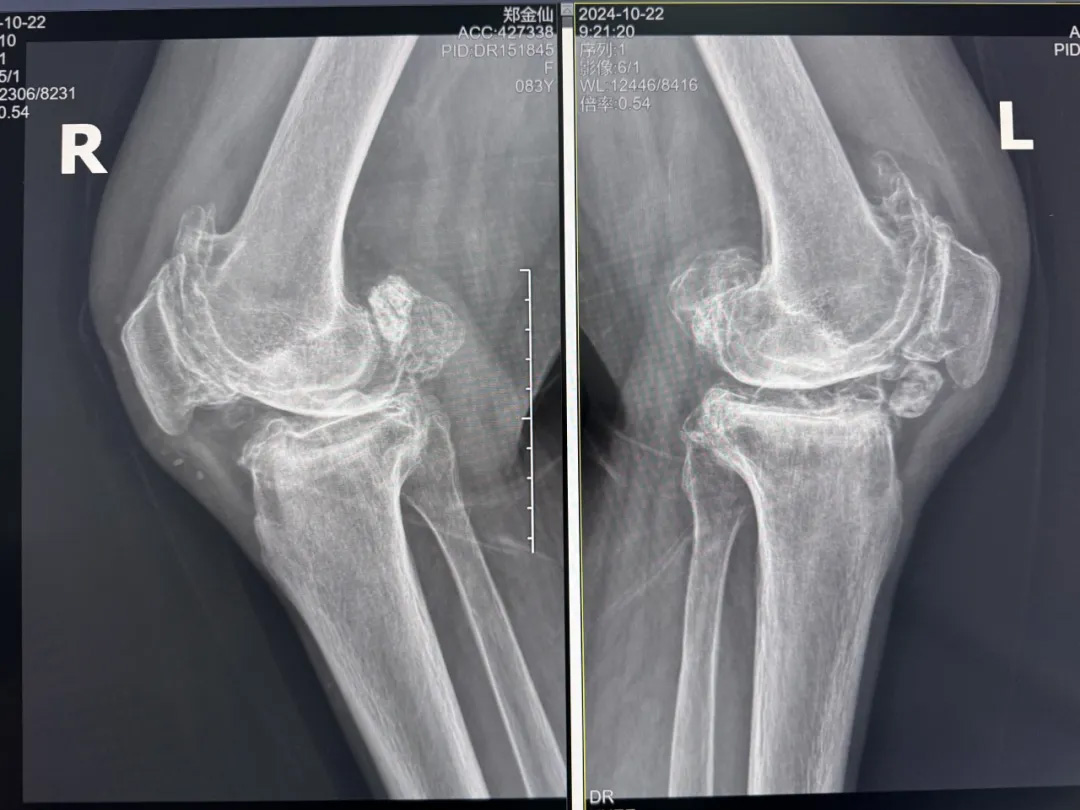

年輕時(shí)愛到處走走的鄭阿婆,晚年卻被雙膝劇痛困在輪椅上長達(dá)二十年。經(jīng)羅副院長診斷,她的膝關(guān)節(jié)軟骨幾乎磨光,關(guān)節(jié)嚴(yán)重畸形,呈"羅圈腿",走幾步便疼痛鉆心,連如廁都需家人抱扶。“我這輩子啊,估計(jì)再也站不起來了。”是阿婆最常說的話。